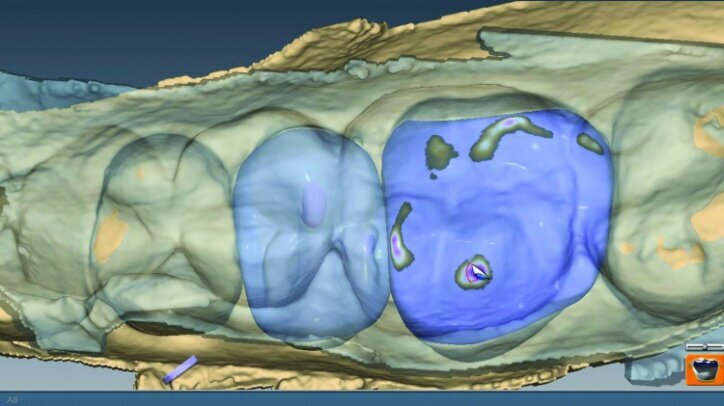

The initial proposals for the restorations were made using Library A and autogenesis, which is morphogenesis of the library tooth with the neighbouring teeth (Figs. 26g–i).

Material thickness of the proposed restorations was checked (Fig. 26j, k). Tools were then utilized to improve the initial proposal to the desired result. The rubber tooth tool was used to make minor adjustments to the anatomy (Figs. 26l–n). The smooth surface tool was used to smooth the surfaces (Figs. 26o, p).

The location and strength of the occlusal contacts were checked and adjusted (Fig. 26q). Interproximal contact strength and location was then verified and adjusted as needed (Fig. 26r).

The final proposals were then verified prior to milling (Figs. 26s, t, w). The slice plane view was used to check the space between the tooth preparation and the restoration (Figs. 26u, v).

This is done to check for possible areas that may prevent the final restoration from completely seating on the preparation or for areas that may be over milled. Over-milling reduces the thickness of the material. This view also illustrates the lack of preparation on the axial wall and the minimally invasive approach taken. The location of the sprues were noted and adjusted as needed in the milling preview (Fig. 26x).